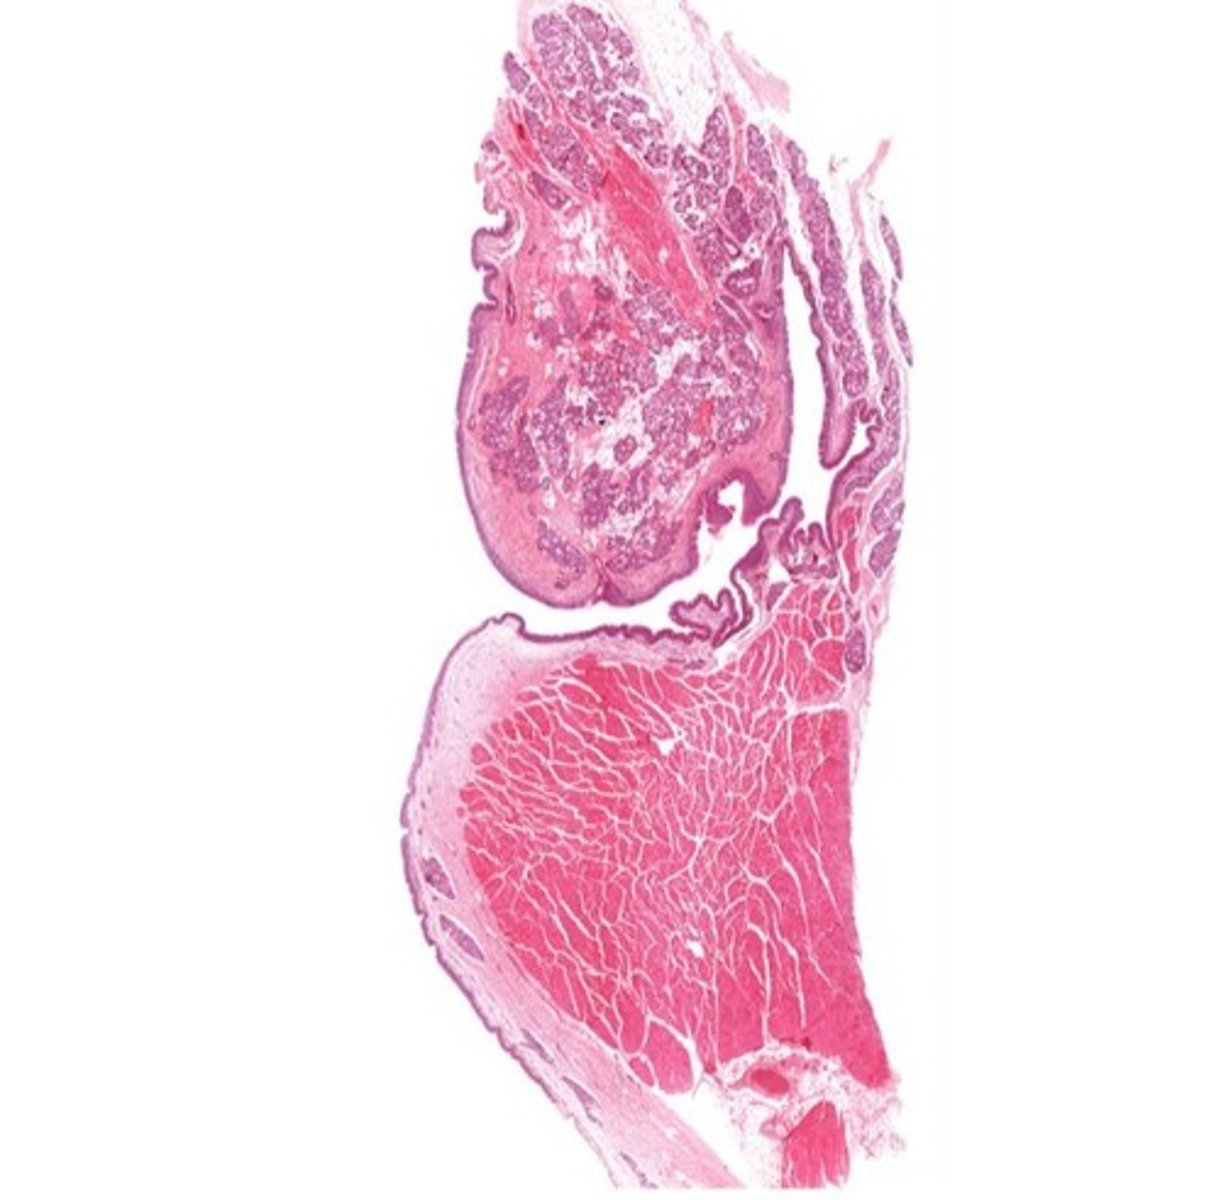

Larynx (voice box)

Identify the entire structure

Describe the transitional epithelium of the larynx

The main transition occurs near the vocal cords, separating the squamous epithelium of the true vocal cords from the respiratory epithelium pseudostratified ciliated